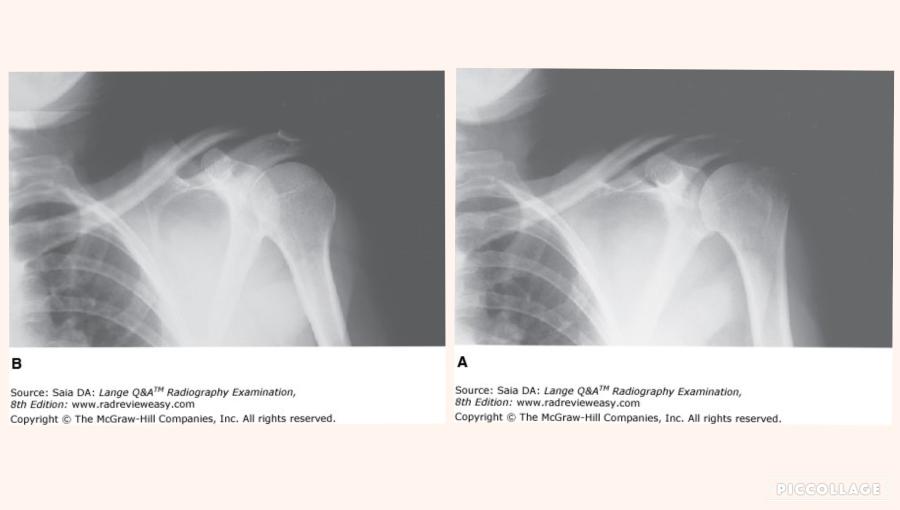

Which of the following statements is (are) true regarding the images shown in Figure 2–33?

- Image A is positioned in internal rotation.

- Image B is positioned in internal rotation.

- The greater tubercle is better demonstrated in image A.

2 and 3 only